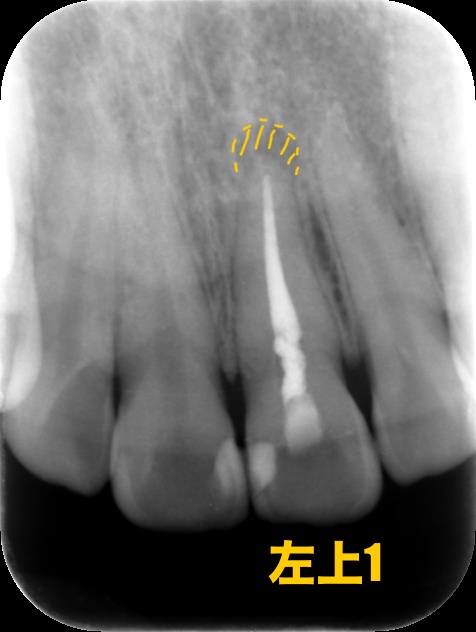

CASE1:【難症例】パーフォレーション(穿孔)をMTAセメントで修復した根管治療

主訴:他院でジルコニア治療後に再発した根尖病変

パーフォレーションのせいでジルコニアを入れた歯に大きな根尖病変が…

根管治療とMTAセメントによるリペア

レントゲン画像にあるように、根管治療を行った後、右上の歯のパーフォレーションにはMTAセメントを使用してリペアしました。

(初診時の影がない部分が骨が溶けている様子です)

内側は骨の壁がなくなるほどごそっと溶けていましたが、一目瞭然でバッチリ回復しています!

処置内容:マイクロスコープによる精密リペアとMTA根管充填

無事、骨も回復し痛みや違和感もなくなったのでオールセラミックスをいれました。当院では、他の歯科医院で抜歯と診断された歯の根管治療を日常的に行っています。高性能な治療器具の導入と、治療時にはアシストする衛生士2人を付けることによって、患者様が安心して治療を受けていただける環境を作っています。